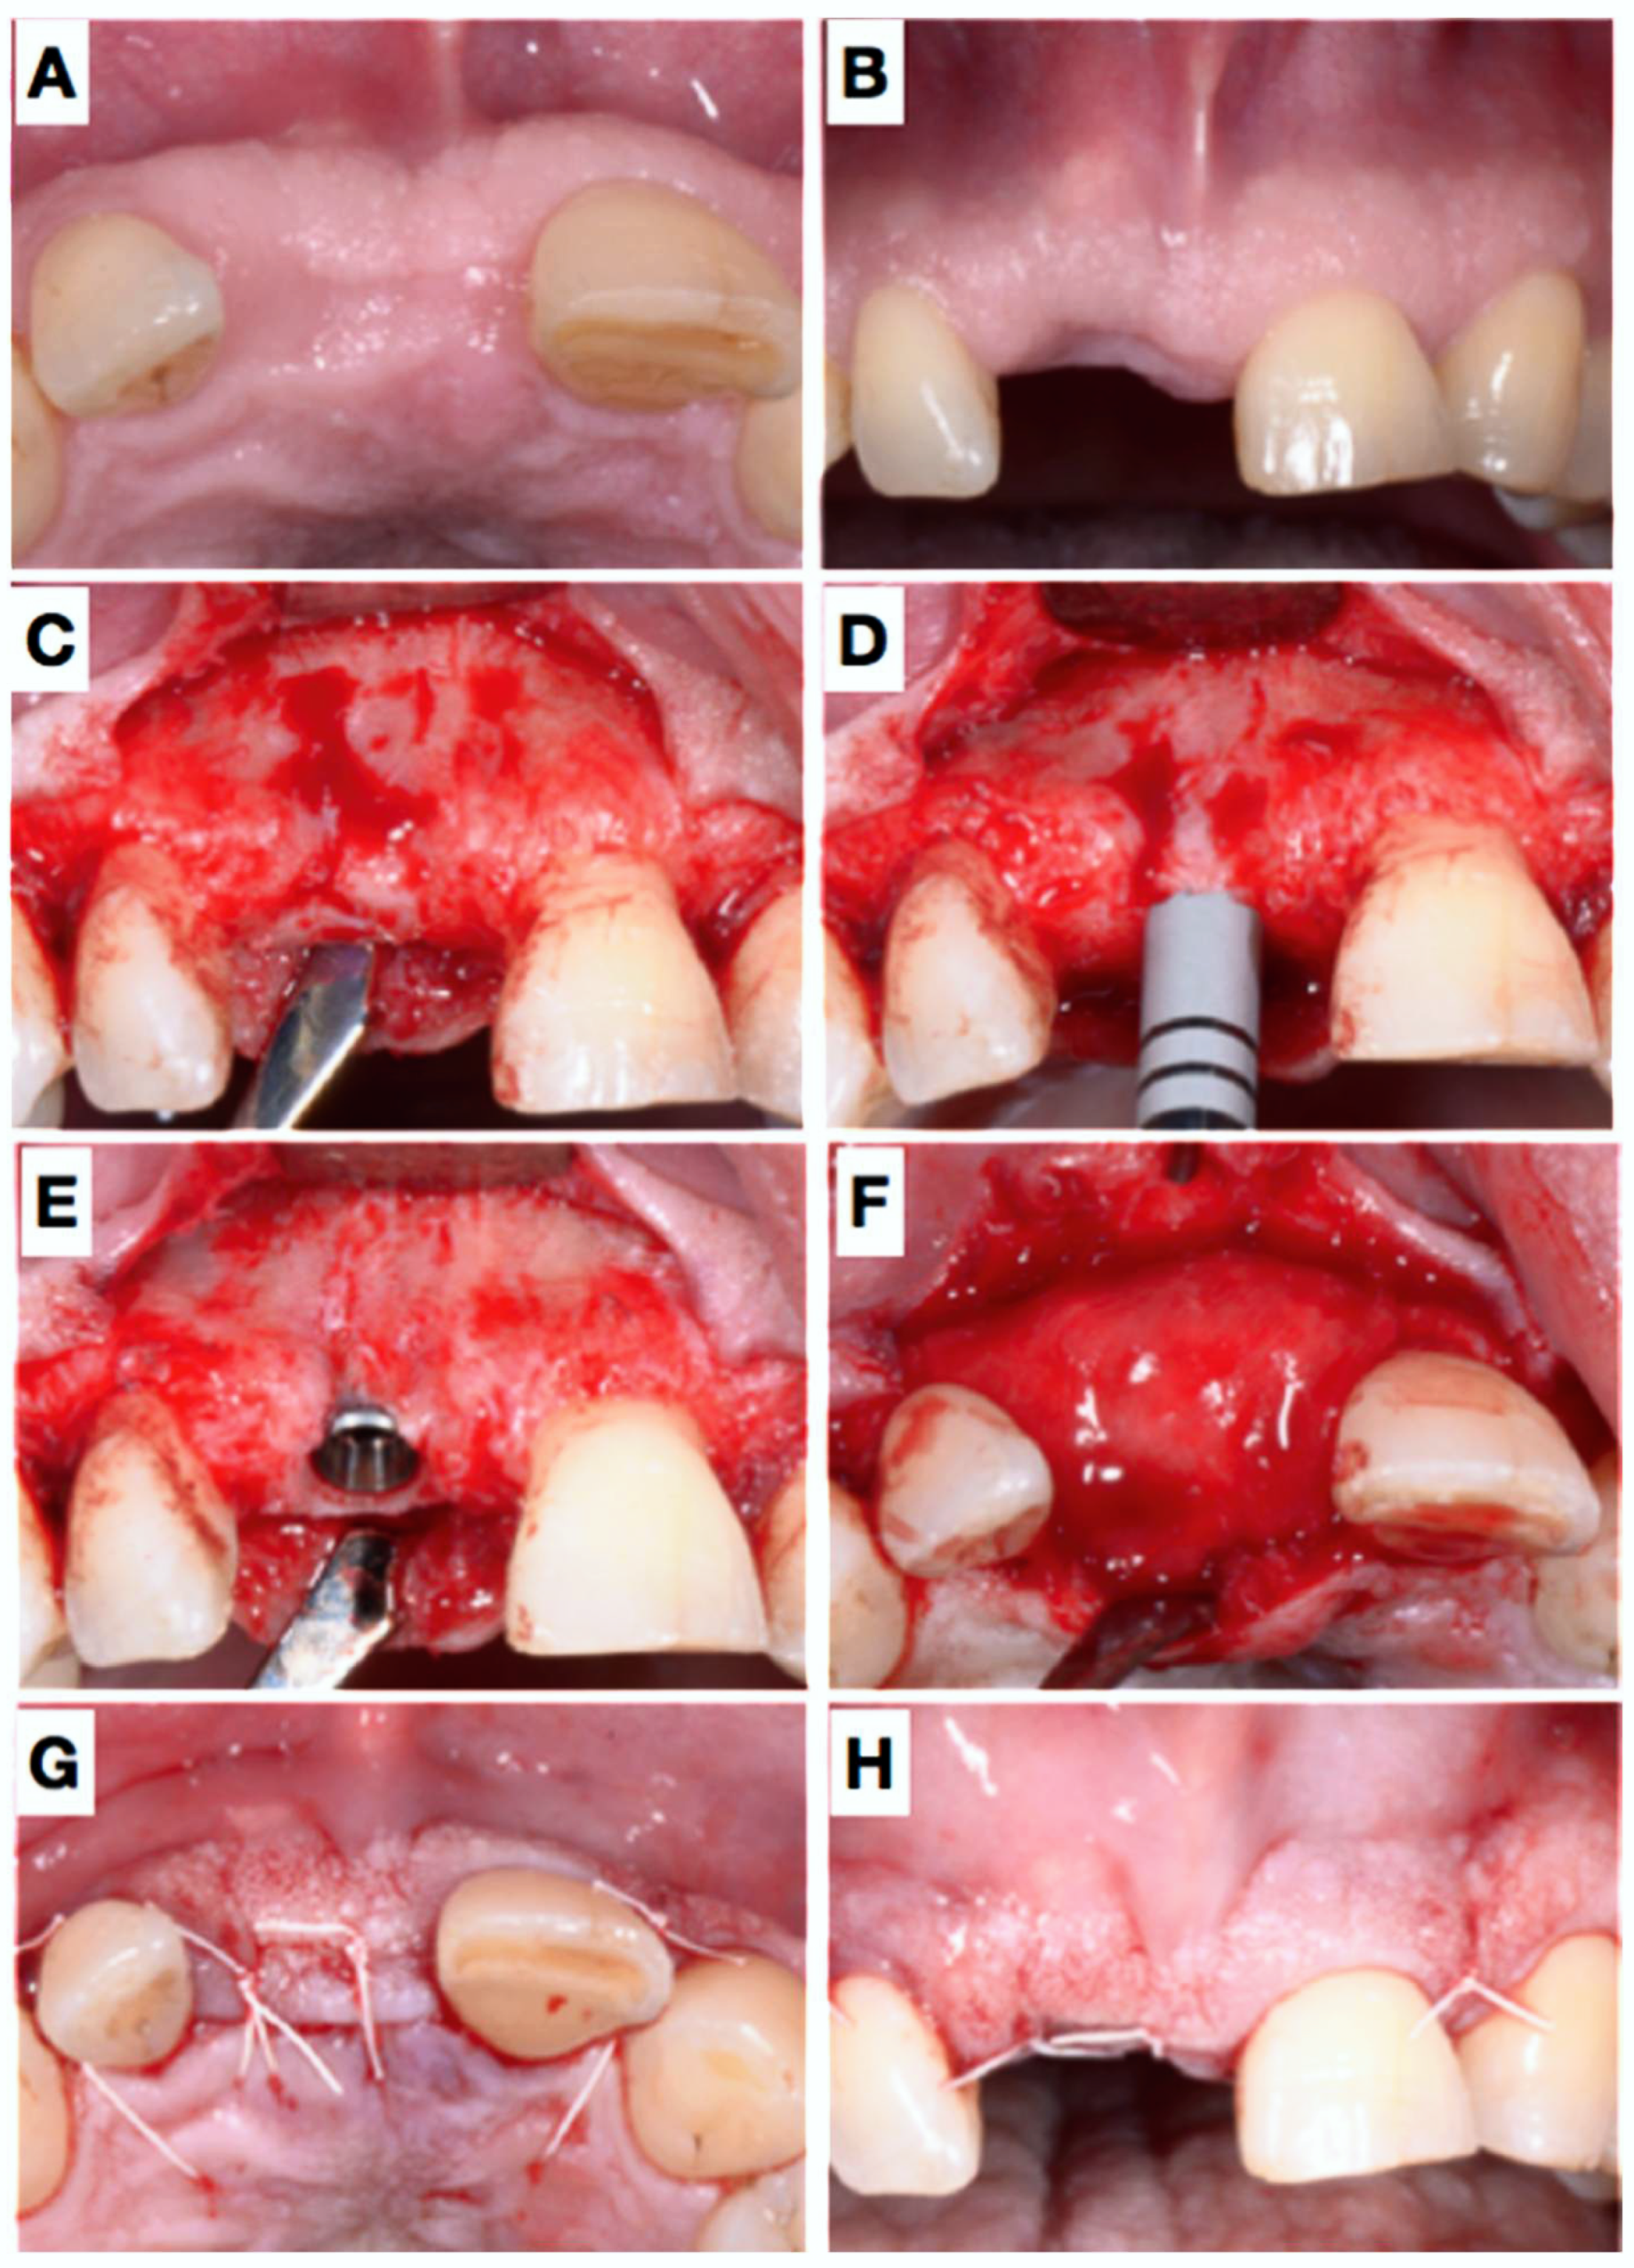

Figure 1.

Pre-operative view of the tooth 11 still in situ (A,B) and after extraction (C). Panel (D) shows clinically the lack of the buccal plate elucidated with the periodontal probe causing local blood circulation impairment due to pressure at the respective apical gingiva. A resorbable rigid membrane was cut in shape (E) and placed under the resorbable collagen membrane (F), unfortunately not clearly visible in the image).